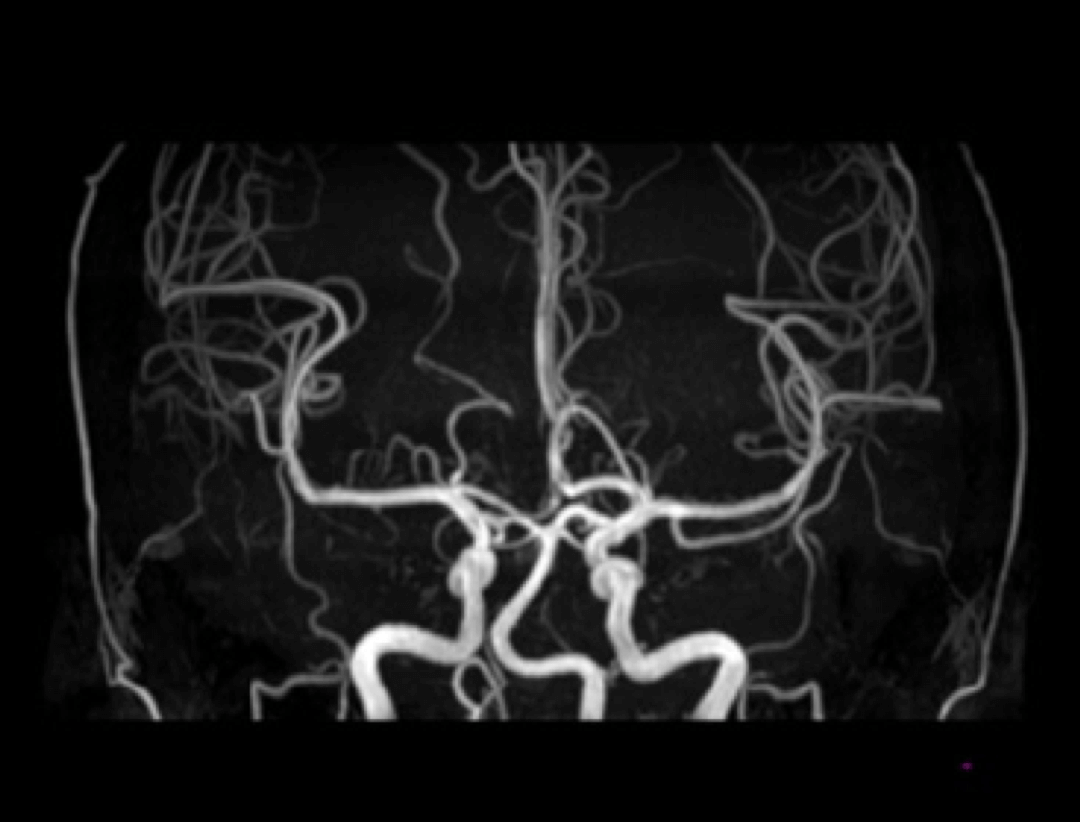

Angiografia